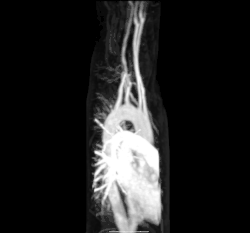

![]() The human circulatory system (simplified). Red indicates oxygenated blood carried in arteries. Blue indicates deoxygenated blood carried in veins. Capillaries join the arteries and veins. | |